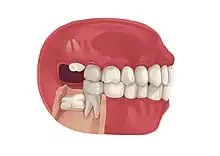

Impacted wisdom teeth is a condition where the third molars (wisdom teeth) are prevented from erupting into the mouth.[1] This can be caused by a physical barrier, such as other teeth, or when the tooth is angled away from a vertical position.[2] Completely unerupted wisdom teeth usually result in no symptoms, although they can sometimes develop cysts or neoplasms. Partially erupted wisdom teeth or wisdom teeth that are not erupted but are exposed to oral bacteria through deep periodontal pocket, can develop cavities or pericoronitis. Removal of impacted wisdom teeth is advised for the future prevention of or in the current presence of certain pathologies, such as caries (dental decay), periodontal disease or cysts. Prophylactic (preventative) extraction of wisdom teeth is preferred to be done at a younger age (middle to late teenage years) to take advantage of incomplete root development, which is associated with an easier surgical procedure and less probability of complications.[3]

Impacted wisdom teeth are classified by the direction and depth of impaction, the amount of available space for tooth eruption, and the amount of soft tissue or bone (or both) that covers them. The classification structure helps clinicians estimate the risks for impaction, infections and complications associated with wisdom teeth removal.[6] Wisdom teeth are also classified by the presence (or absence) of symptoms and disease.[7]

Impacted wisdom teeth are often described by the direction of their impaction (forward tilting, or mesioangular being the most common), the depth of impaction and the age of the patient as well as other factors such as pre-existing infection or the presence of pathology (cysts, tumors or other disease).[5]: 143–144 Each of these factors is used to predict the difficulty (and rate of complications) when removing an impacted tooth, with age being the most reliable predictor[8] rather than the orientation of the impaction.[9]